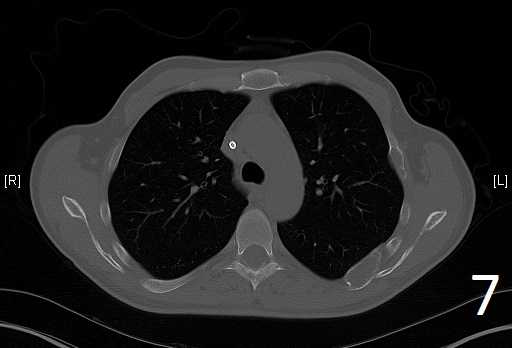

CT

• Useful to determine the extent of the lesion as well as ground glass appearance (Fig. 2-3)

Fig. 6

Fig. 7

Fig. 6-7. Axial CT reconstruction of the chest showing lytic and expansile lesion of the left scapula and ribs (polyostotic fibrous dysplasia).